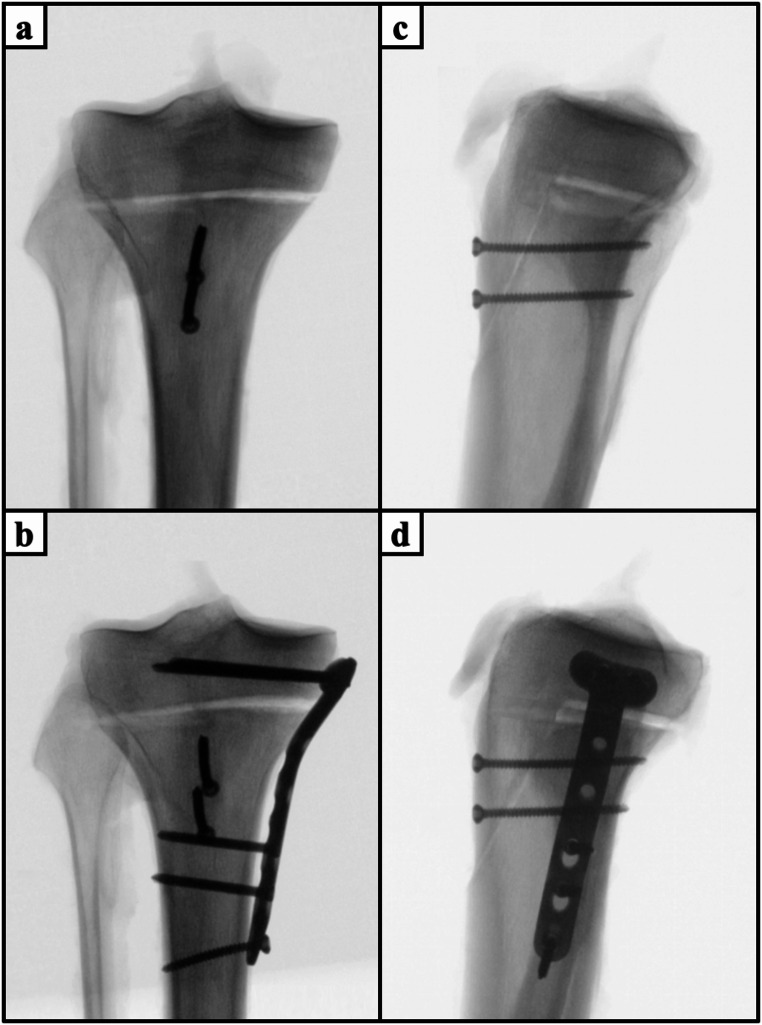

Methods: Two different types of apoepiphyseal tibial tubercle avulsion fractures were created in 40 proximal tibiae according to the modified Ogden classification: (1) Ogden type IIIA and (2) Ogden type IV. The fractures were fixed with either isolated apophyseal screws or additionally with a medial plate or epiphyseal screws. All specimens were biomechanically tested under progressively increasing cyclic loading until failure, while capturing the interfragmentary movements with motion tracking.

Results: Augmentation of apophyseal screw osteosynthesis by a medial plate in Ogden IV fractures or epiphyseal screws in Ogden IIIA fractures exhibited significantly higher cycles to failure and failure loads (P< 0.05), and significantly less axial displacement (P < 0.05) compared to isolated apophyseal screw fixation. Fixation of Ogden type IIIA fractures resulted in significantly less axial displacements and higher construct stiffness, cycles to failure and failure loads compared to Ogden type IV fracture (P < 0.001). Fracture gap opening did not differ significantly between the fixation techniques.